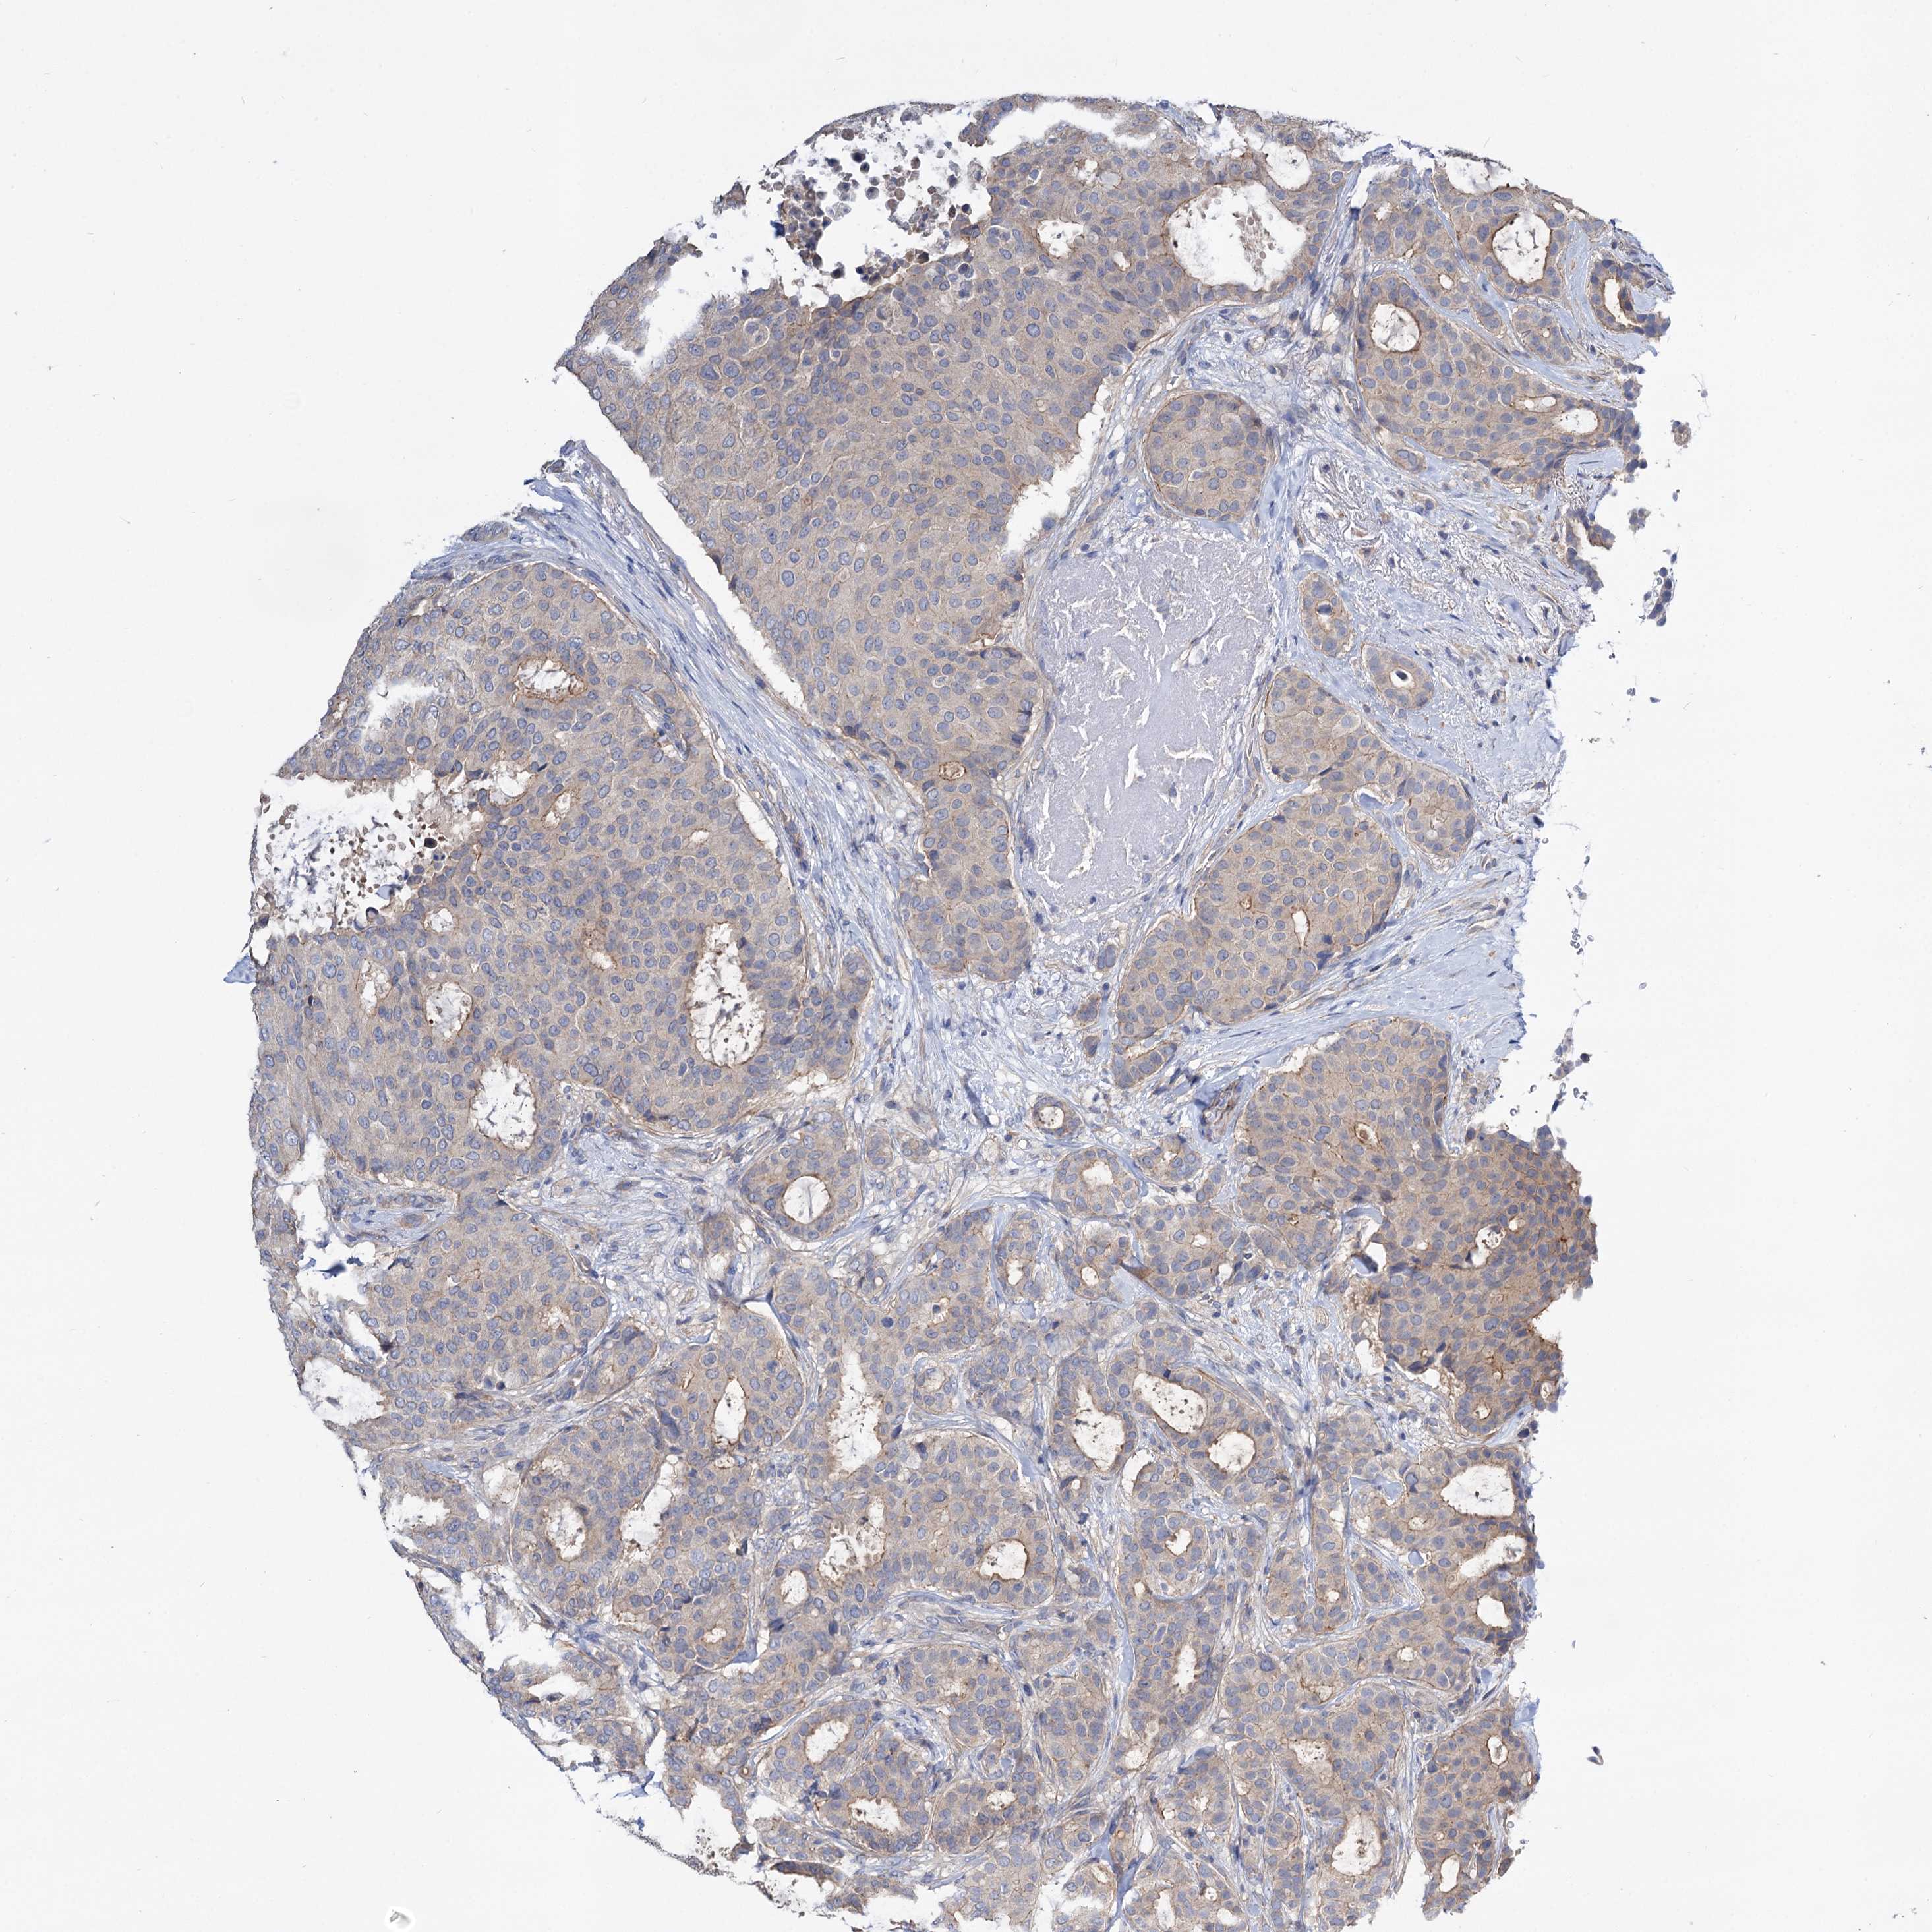

CANCER BREAST CANCER Show tissue menu

BRCA TCGA BRCA VALIDATION PROTEIN EXPRESSION